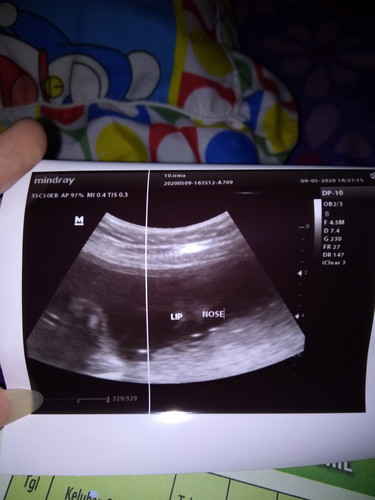

Ada yng sama Hpl 13 agustus ? Udah ngerasain apa aja ?

Saya 13 Agustus Ngrasain di tinju si dedek kadang perut miring kesundul entah pala ato kaki :')